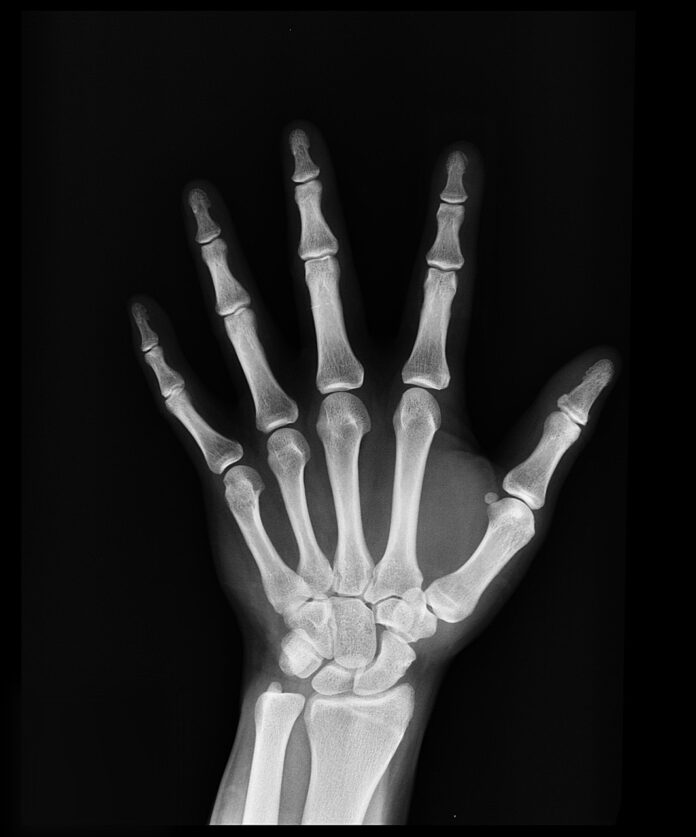

Problém s nedostatečnou kapacitou specialistů na kostní metabolismus – osteologů – řeší právě Populační program časného záchytu osteoporózy. Vyšetření kostí mohou díky němu již téměř rok provádět také proškolení praktičtí lékaři a gynekologové. Pacienti v rizikové skupině nejprve v rámci dvouletých preventivních prohlídek absolvují pohovor a vyplní diagnostický dotazník. „Týká se to žen rok po menopauze až do věku 59 let a mužů od 65–69 let. Lékaři u nich vyhodnotí riziko osteoporózy, a pokud je vysoké, pacienti následně podstoupí denzitometrii – podrobné vyšetření kostí,“ upřesňuje MUDr. Šonka a dodává, že ženy nad 60 let a muži nad 70 let mají na vyšetření pomocí denzitometru nárok už při všech preventivních prohlídkách.

Před startem programu časného záchytu bylo v Česku dostupných asi 100 denzitometrů, což je přibližně polovina ve srovnání se standardem zemí Evropské unie. Jedním z cílů populačního programu tak je do roku 2026 síť denzitometrů zdvojnásobit. „Vzhledem k tomu, jak rychle jich přibývá, se to podle mě podaří už v letošním roce,“ říká MUDr. Šonka, který denzitometr využívá také. Ideální stav podle něj nastane, až bude na 50 000 obyvatel dostupný alespoň jeden takový přístroj.

Denzitometry v současné době chybí hlavně v regionech; ve větších městech, například v Praze a v Brně, jich už je dostatek. „Důležitý je jak včasný záchyt pacientů v méně závažném stadiu osteoporózy, tak prokázání tohoto onemocnění v případě podezření,“ doplňuje MUDr. Ivo Procházka, člen výboru Sdružení praktických lékařů. Vyšetření pomocí denzitometru začal pacientům nabízet na začátku letošního roku a doposud jich provedl asi 250. „Jakmile známe výsledky, pacienty poučíme o rizicích, která jim hrozí. Vysvětlíme jim také, jak by měl vypadat jejich životní styl a stravovací návyky, a doporučíme vhodnou terapii. Tím vším se snažíme předejít nepříjemným zlomeninám, které osteoporóza způsobuje. Jejich léčba je náročná, zdlouhavá a bolestivá. V mnoha případech navíc s trvalými a život ohrožujícími následky,“ říká MUDr. Procházka.